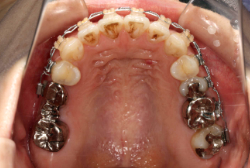

混合歯列期から治療開始した側方拡大による非抜歯症例

「配列の凸凹を治したい」という主訴で来院したケースです。診断の結果、永久歯がすべて生えそろうと、かなり厳しい叢生(歯並びの凸凹のことです)になる可能性が高いと判明しました。原因としては特に上の顎の骨が小さいため、歯を収容する容量不足になっていると診断しました。このケースの場合は、成長発育期に治療開始しますので、顎の骨を土台ごと大きくすることが可能です。

そこで、まず急速拡大装置を使用して上顎骨の拡大を行い、上顎骨の容量が拡大したことを確認後、マルチブラケット装置を使って全体の修正をする、と言う二段階の作戦をとることになりました。

この時期に使う急速拡大装置は、適切な診断に基づいて正しく使用することで確実に骨を大きくすることができます。拡大することで隙間が確保できるので、永久歯の抜歯を避けることができます。

急速拡大装置を1日1回装置の中央にある拡大ネジを、ご自身で回して頂くことで25日間くらいかけて、6mmほど拡大しました。拡大後は、上顎の前歯の隙間が広がっていることがお分かりいただけると思うのですが、土台の骨ごと広がるのでこのような隙間ができます。その後1年半くらいマルチブラケット装置を使用して、全体の修正を行いました。

結局、歯の本数を減らすことなく、すべてご自分の歯を残して正しい配列にすることができました。このケースの場合、2009年10月より拡大と経過観察を行い、2012年3月より1年2ヶ月マルチブラケット装置を装着、2013年5月に治療を終了しました。2段階で行う治療としては短期間で終了しているケースと思います。